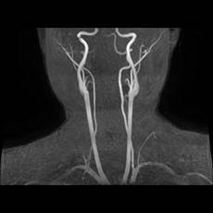

3T MRIを用いた脳ドックも行っています。

脳ドックは、脳の病気を未然に防ぐことを目的とした予防的な検査です。

脳・脳血管・頚部血管を詳しく調べ、

などの有無を確認し脳梗塞やクモ膜下出血を発症する前にリスクを発見できる可能性があります。

自覚症状のない段階での早期発見・予防に役立ちます。